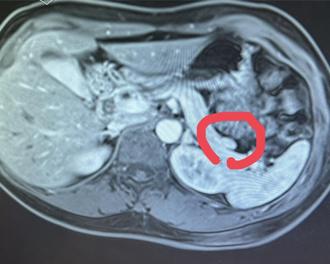

40歲的邱姓女子每天早晨昏沉爬不起來,隨著症狀日益嚴重,空腹就會神智模糊、胡言亂語,直到進食後才恢復正常。求助多家醫院的中、西醫仍查不出病灶,最後找對科別與檢查,才發現是罹患罕見的胰島素瘤,上個月底接受切術手術,目前恢復狀況良好。